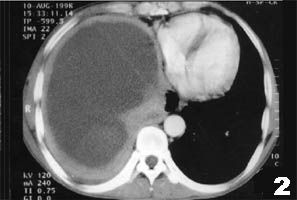

(1)X线胸片:干性胸膜炎患侧仅肋膈角变顿,渗出性胸膜炎中等量以上积液可见大片均匀致密影,其上缘呈从外上向内下的弧形,肋膈角消失,膈影及心影不清。大量积液时纵膈向健侧移位,肋间隙变宽,膈肌下降。 医学百科网 | YxBaike.Com